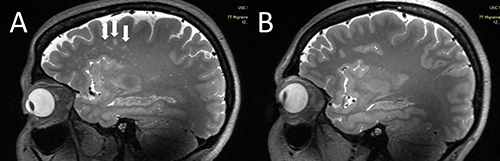

New magnetic resonance imaging (MRI) research suggests a significant link between deep white matter hyperintensity severity and increased quantity of enlarged perivascular spaces in the centrum semiovale among people with migraines.